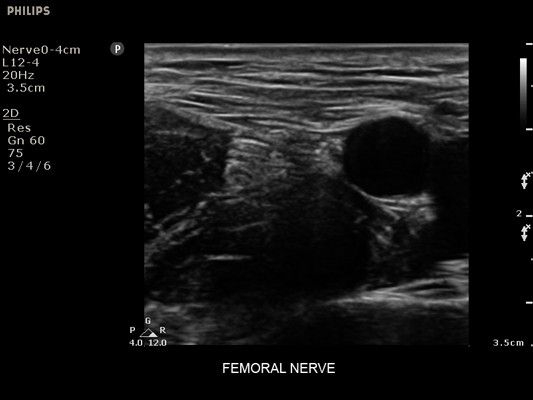

• Сосудистый доступ

• Диагностика нервов

• Линейный УЗИ датчик Philips L12-4